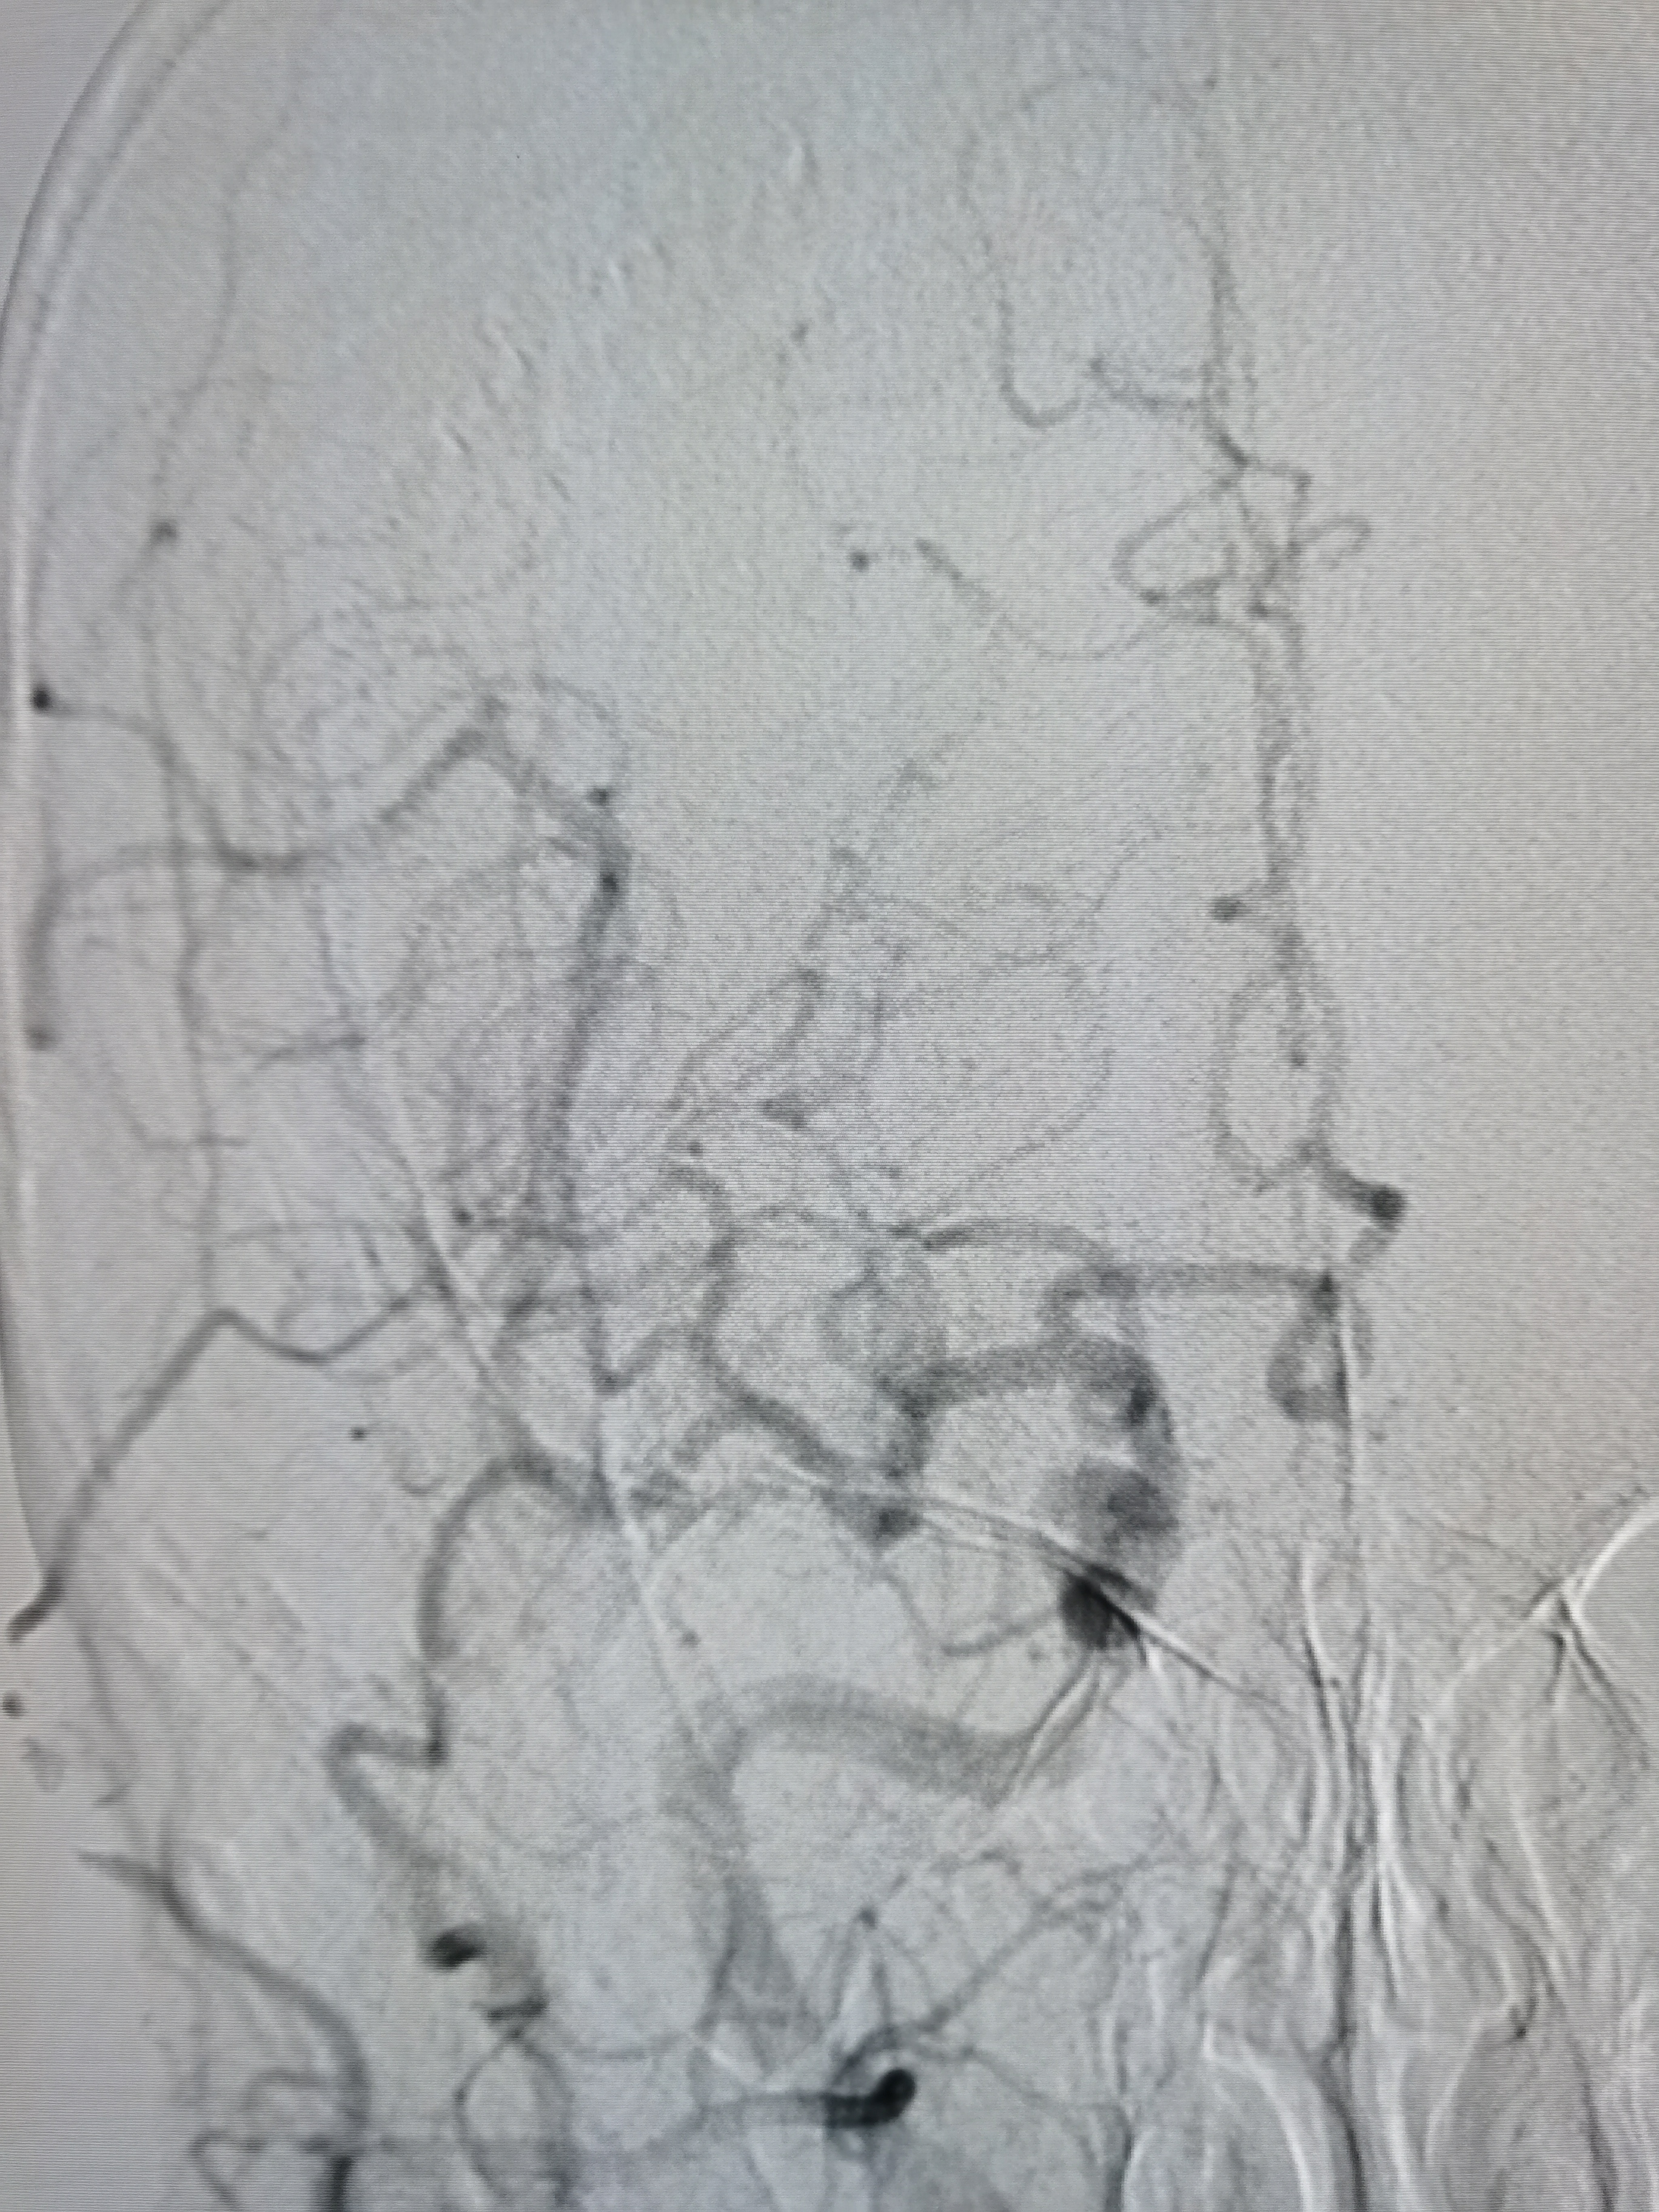

将8F导引导管送至左侧锁骨下动脉近左椎动脉起始部,微导丝顺利通过病变,2.0/20球囊预扩病变。

3、手术过程中,先用小球囊扩张病变,观察血栓情况,及时应用支架全程覆盖血栓及病变部位,成形满意。